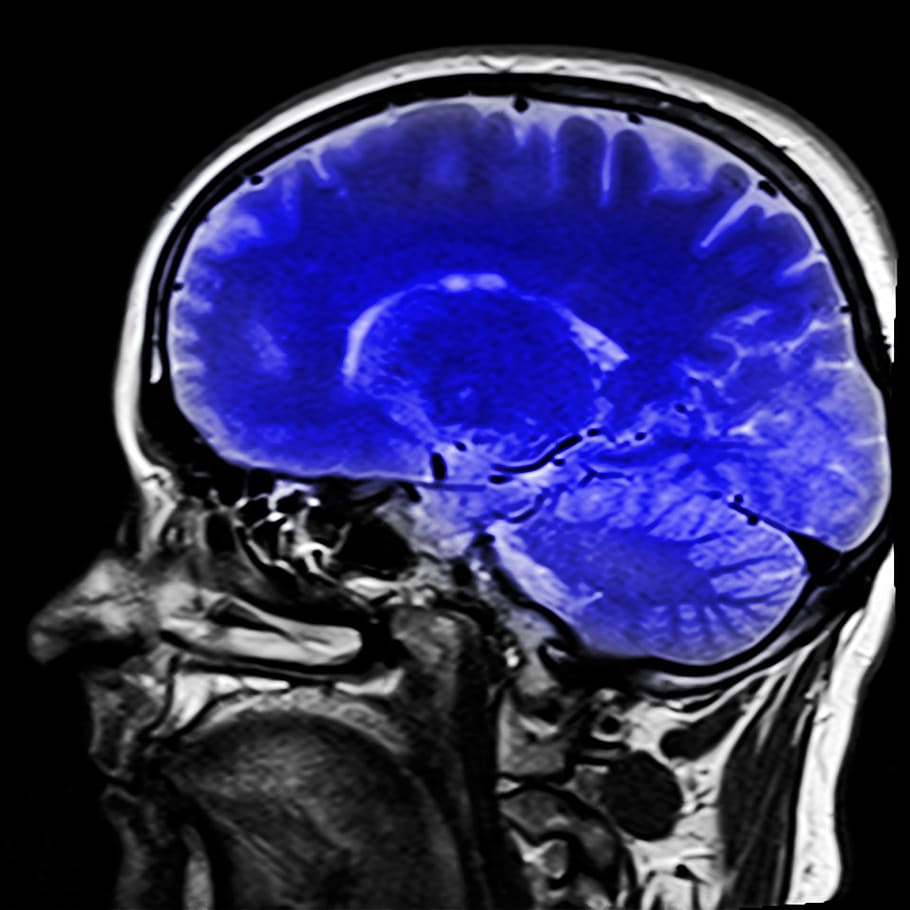

head-magnetic-resonance-imaging-mrt-x-ray.jpg

我们的大脑是由坚硬的颅骨保护的脆弱器官,但有时也需要额外的保护